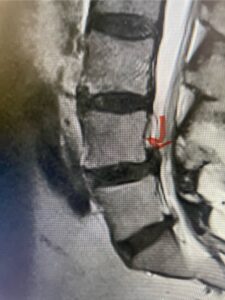

This 54-year-old morbidly obese female presents with progressive back and leg pain and quadriceps weakness. She had no diabetes. She failed all means of conservative management including physical therapy and epidural injections. On imaging she had severe stenosis at L3-4 with a disc protrusion and a slight grade 1 spondylolisthesis at L3-4 (Fig 1). We performed dynamic lumbar x-rays which demonstrated instability at L3-4 and L4-5 (Fig 2). The patient wished to have surgery. We performed an L2-4 decompressive laminectomy and L3-5 in situ fusion because of her instability. Post operatively the patient had relief of leg pain, although the patient was slow to mobilize.

Fig 1b: Axial lumbar T2-weighted MRI demonstrating severe lumbar stenosis (red dot)